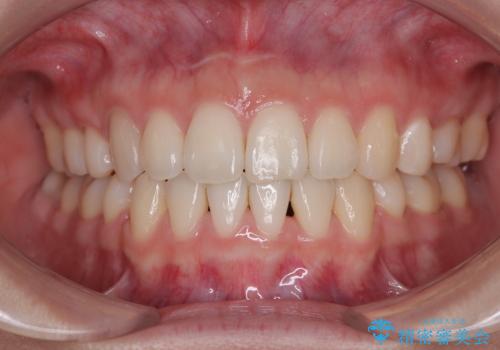

【非抜歯】上下の前歯が噛み合わないオープンバイトの治療

開咬と前方に飛び出した前歯 インビザラインによる矯正治療

担当医 藤巻太一朗